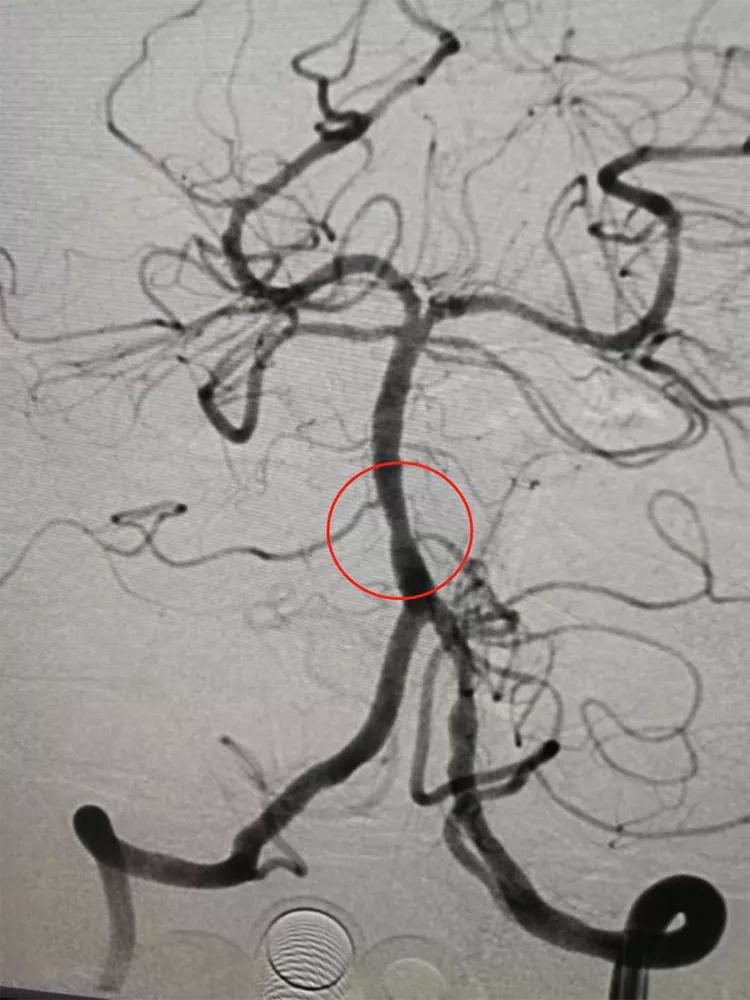

患者男性,76岁,反复发作性头晕、行走不稳2月余入院。发作时头晕,头重脚轻,伴有言语含糊、肢体乏力等症状,持续数分钟到数十分钟可以自行缓解。门诊检查发现基底动脉重度狭窄,规范服药保守治疗,症状仍然反复发作。入院查体:神清,构音清晰,四肢肌力正常。入院诊断:短暂性脑缺血发作;基底动脉重度狭窄。入院后经基底动脉支架成形术治疗,患者头晕等症状再无发作。

支架成形术前,基底动脉下段重度狭窄

支架成形术后,基底动脉狭窄解除